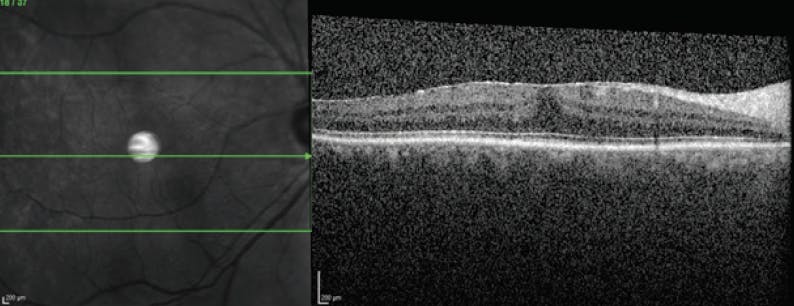

Vitreous Opacities With Progressive ERM—and 20/20 VA

A middle-aged phakic man presented to my clinic. He was a professional photographer who reported symptomatic vitreous opacities (VOs). Clinical examination including OCT (Figure 1) showed that he had 20/20 VA, no signs of cataract, bilateral posterior vitreous detachment (PVD), and average floaters. I advised that he wait 6 months before considering surgery.

The patient returned in 5 months reporting that his VOs had worsened and that neither eye was noticeably worse than the other. OCT imaging of the patient’s right eye (OD) showed the presence of an epiretinal membrane (ERM) and the loss of foveal contour (Figure 2); the left eye (OS) was unchanged. The patient continued to have 20/20 VA.

The patient reported that he was unable to perform his photography duties. The patient and I had a thorough conversation about the risks and benefits of surgery to address his visual disruption, and he was passionate about undergoing surgery OD.

Pars plana vitrectomy was performed OD. Per my usual methodology, I aimed to remove only the tissue easily reached (ie, what was detached and available). After removal of vitreous, I used forceps to initiate an ERM peel.

The patient remained 20/20 on postoperative day 1. By postoperative week 5, foveal contouring had begun to return OD (Figure 3). Like most patients who have had successful surgery for the removal of symptomatic VOs, he is eager to undergo surgery in the contralateral eye.